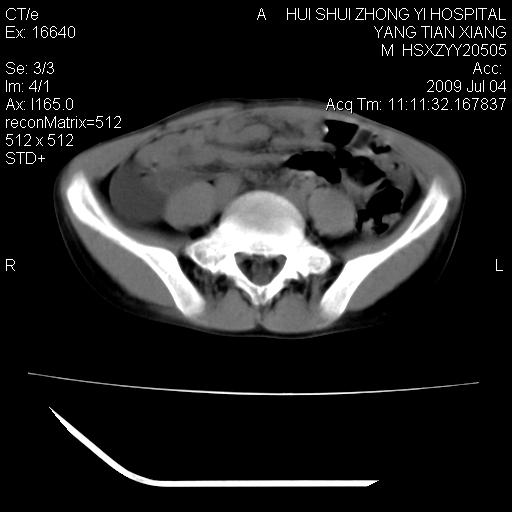

肝右叶胆管内见条状高密度影,脾脏增大,双肾上腺无异常;右肾正常结构消失,其实质内见类圆形低密度灶,ct值范围0-6hu,界清,右输尿管全程伴行多发低密度灶,界清,膀胱壁增厚,腹盆腔未见确切肿大淋巴结。

考虑:1、肝内多发胆管结石并肝内胆管扩张。2、右肾、输尿管多发脂肪瘤,多发平滑肌瘤?建议ct增强检查。4、膀胱壁增厚。

右侧巨输尿管可能。

2、右侧巨输尿管并右肾积水可能性大。

右侧巨输尿管并神谕积水,左肾代偿性肥大,脾大,肝内胆管多发结石并胆管扩张。